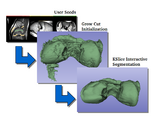

CarreraSlice is an interactive segmentation tool. It combines a fast implementation of the GrowCut algorithm for the 'initialization' phase with KSlice, an interactive algorithm based on Level Sets, for the 'refinement' stage.